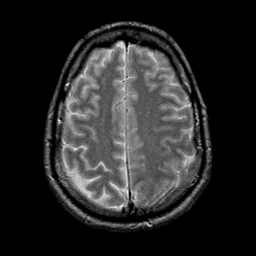

glioma overlay -- Slice #21

[Home][Help][Clinical] Slice 21

Click on sagittal image to select slice. Click on thin tickmark to change timepoint, or thick tickmark for overlay.